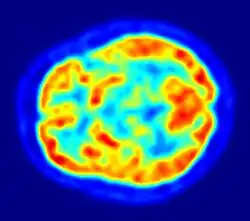

Although the human brain represents only 2% of the body weight, it receives 15% of the cardiac output, 20% of total body oxygen consumption, and 25% of total body glucose utilization.[138] The brain mostly uses glucose for energy, and deprivation of glucose, as can happen in hypoglycemia, can result in loss of consciousness.[139] The energy consumption of the brain does not vary greatly over time, but active regions of the cortex consume somewhat more energy than inactive regions, which forms the basis for the functional neuroimaging methods of PET and fMRI.[140] These techniques provide a three-dimensional image of metabolic activity.[141] A preliminary study showed that brain metabolic requirements in humans peak at about five years old.[142]

Functional neuroimaging techniques show changes in brain activity that relate to the function of specific brain areas. One technique is functional magnetic resonance imaging (fMRI) which has the advantages over earlier methods of SPECT and PET of not needing the use of radioactive materials and of offering a higher resolution.[156] Another technique is functional near-infrared spectroscopy. These methods rely on the haemodynamic response that shows changes in brain activity in relation to changes in blood flow, useful in mapping functions to brain areas.[157] Resting state fMRI looks at the interaction of brain regions whilst the brain is not performing a specific task.[158] This is also used to show the default mode network.